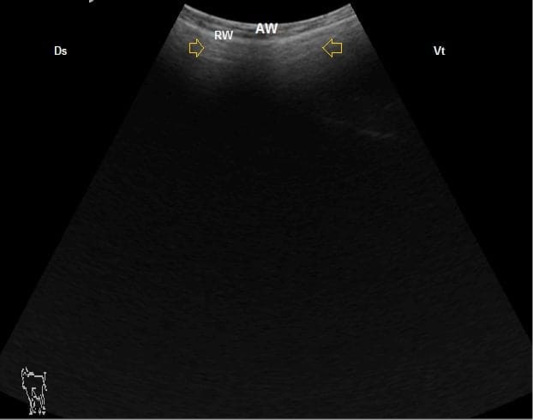

B. Mode ultrasonographic image of ruminal frothy tympany. The small gas gap appeared as reverberation artifact (arrows) medial to the ruminal wall (RW), AW: Abdominal wall, Ds: Dorsal, Vt: Ventral.